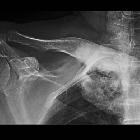

Sklerosierung der Klavikula

Sclerotic

clavicle • Sternoclavicular hyperostosis - Ganzer Fall bei Radiopaedia

clavicle • SAPHO syndrome - Ganzer Fall bei Radiopaedia

Sclerotic clavicles have many causes:

- trauma: fractured clavicle

- arthritis: osteoarthritis, seronegative arthritides

- osteitis condensans of the clavicle

- SAPHO syndrome

- clavicular tumors

- tumor-like lesions

- metabolic bone disease

- congenital

- Friedrich disease